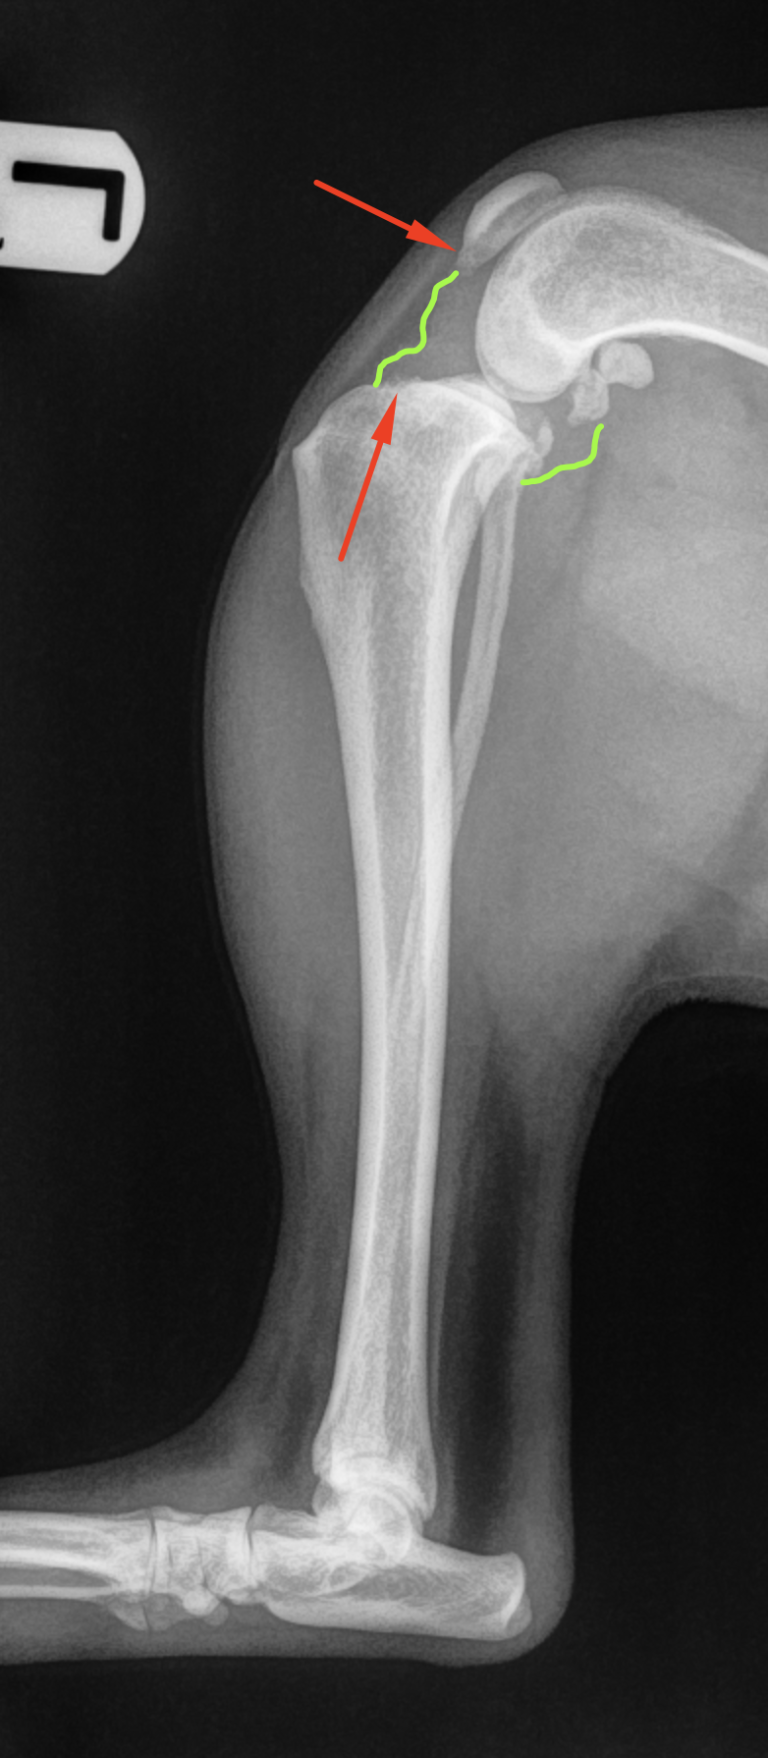

From mooresortho.com

TPLO for Cruciate Ligament Ruptures Moores Orthopaedic Clinic Tplo Surgery Gone Wrong tplo surgery is known for its immediate effectiveness in reducing pain and improving joint stability in dogs with. full recovery from tplo surgery depends on the severity of lameness before surgery, degree of ccl tear (partial or full), presence or absence of. discover the essentials of tplo surgery for dogs, including how often complications occur, risk factors,. Tplo Surgery Gone Wrong.